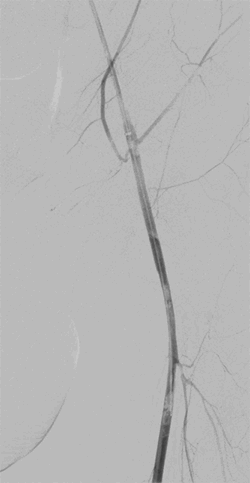

There was no distal flow in either of the lower extremities. A large fistula was noted on the left between the left common femoral artery and common femoral vein near the femoral bifurcation with minimal flow through the left superficial femoral artery. A 6 mm x 38 mm covered balloon-expandable stent-graft was deployed across the fistula. An arteriogram was performed, which showed complete exclusion of the AVF with a patent lumen into the left common femoral artery (Figure 3).

Figure 3. Angiogram after left sided stent deployment in the left common femoral artery. AVF no longer visualized.